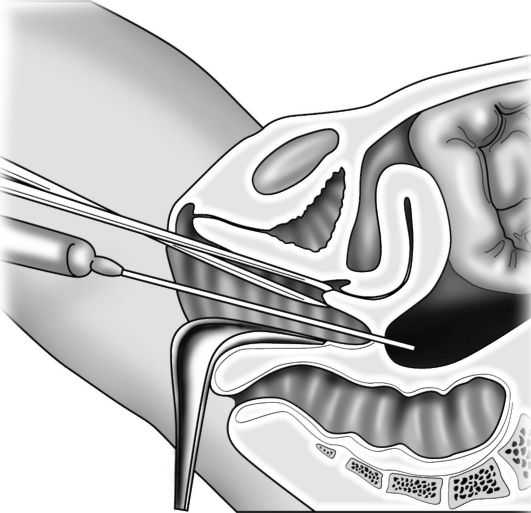

Омоложение (biorevitalization) влагалища и промежности. Неинвазивное эффективное лечение ранних, начальных форм опущения половых органов заключается во введении специальной гиалуроновой кислоты в стенки влагалища, промежности. Манипуляции проводятся под местным обезболиванием. Профилактика дальнейшего прогрессирования заболевания.

Неинвазивное эффективное лечение ранних, начальных форм опущения половых органов заключается во введении специальной гиалуроновой кислоты в стенки влагалища, промежности. Манипуляции проводятся под местным обезболиванием. Профилактика дальнейшего прогрессирования заболевания.

Пластика влагалища, совмещенная со слинговой операцией, предназначена не только для коррекции размеров влагалища, но и для лечения стрессового недержания мочи.

Чаще всего опущение или выпадение стенок влагалища происходит вследствие тяжелых естественных родов или родов крупным плодом. Опущение передней стенки влагалища сопровождается перемещением мочеиспускательного канала и мочевого пузыря, что может привести к частым циститам, стрессовому недержанию мочи, частым мочеиспусканиям. При опущении передней стенки влагалища у женщин обостряются хронические вагиниты, поскольку происходит постоянное нарушение флоры. Консервативное лечение воспаления слизистой влагалища в таком случае, как правило, не приводит к успеху, так как необходимо устранить причину заболевания и применить хирургический метод лечения.

ОСОБЕННОСТИ ОПЕРАЦИИ И ПОСЛЕОПЕРАЦОННЫЙ ПЕРИОД

Пластика передней и задней стенок влагалища с одномоментной установка сетчатого импланта (слинг-системы) позволяет избавиться от перечисленных тревожных симптомов, восстановить положение матки, уретры, мочевого пузыря и укрепить мышцы тазового дна. Имплант обладает 100% биосовместимостью с тканями человеческого организма.

Операция проводится под наркозом и длится от 30 до 60 минут. В снятии швов нет необходимости благодаря специальному рассасывающемуся материалу, который применяют наши хирурги при их формировании.

Омоложение влагалища

«Омоложение влагалища» включает в себя компоненты перинеопластики и вагинопластики и проводится для лечения «широкого» влагалища. Эти процедуры являются не чем иным, как модификациями существующих хорошо зарекомендовавших себя методов реконструктивной хирургии влагалища и тазового дна при кольпоперинеорафии, чтобы изменить калибр влагалища за счет уменьшения диаметра влагалищного канала наряду с реконструкцией тела промежности [23].

Используемые хирургические методы могут включать рассечение с помощью традиционных скальпелей или с использованием различных источников энергии, таких как лазер, радиочастота или ультразвук. Различные методы, использующие разные источники энергии, заявили о лучших хирургических результатах с уменьшением заболеваемости, рубцевания и благоприятными исходами в отношении размера и чувствительности влагалища. Однако никакие исследования не подтверждают их превосходство по сравнению с традиционным скальпелем и монополярным игольчатым электродом.

Вагинопластика предназначена для хирургического сужения влагалищного канала и включает удаление избыточной слизистой оболочки влагалища из сводов влагалища.Он может включать переднюю кольпорафию, заднюю кольпорафию, иссечение латеральной слизистой оболочки влагалища или различные комбинации этих хирургических методов (рис.). Некоторые хирурги также проводят пластику леватора по средней линии, чего, по нашему мнению, лучше всего избегать, так как это может вызвать выраженную диспареунию.

Безоперационные энергетические процедуры

Энергетическая кольпорафия включает использование лазеров или радиочастотной (РЧ) энергии для улучшения качества ткани стенки влагалища путем стимулирования роста нового коллагена и эластина, аналогично омоложению кожи, которое выполняется практикующими эстетиками.Цель этих процедур — «сузить» вагинальный канал, делая ткани более эластичными и устойчивыми к разрывам. Радиочастотные процедуры полностью неинвазивны, поэтому нет нарушения барьерной функции, а восстановление минимально [24, 25].